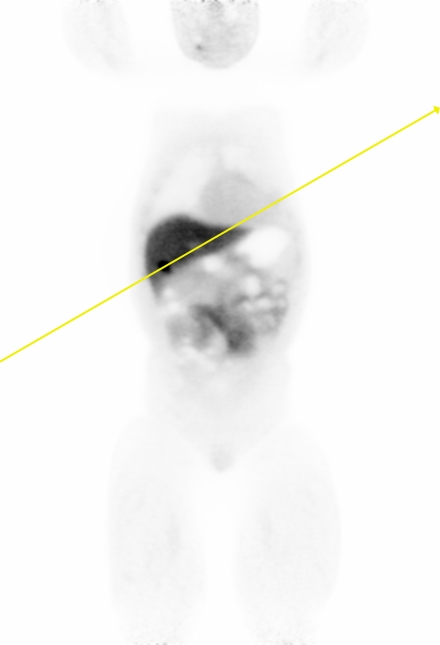

In this section, we present the results of our \acFDG-trained \acDLSE model applied to \acPSMA to evaluate its ability to generalise to radiotracers not included in the training data.

Figure 9 shows two clinical \acPSMA dataset examples. The first dataset illustrates a patient with a prostate lesion and shows good agreement between the \acDLSE and \acSSS corrected \acPET images for both the organs and the lesion.

The second patient example features two adjacent liver lesions; one with a higher and one with a lower activiy level compared to the background liver activity. The \acDLSE-corrected image shows higher activity levels in both the liver and the lesions. Based on a \ac3D manual segmentation of the liver and the FLAB segmentation of the lesions, the contrast values were found to be similar for \acDLSE and \acSSS, with values of and , respectively, for the necrotising lesion, and and , respectively, for the active lesion. These values compare with contrasts of and , respectively, in the non-scatter-corrected image.

| No correction | DLSE | SSS | Profiles |

![]() |

| Sex | Weight | Dose | Coincidences | |

| 1st row | Male | 82 kgs | 202 MBq | 743 millions |

| 2nd row | Male | 73 kgs | 198 MBq | 738 millions |

Finally, Figure 9 shows visually similar results between \acDLSE and \acSSS-corrected images. Furthermore, \acSUVmax values were found to be similar between the two methods (Figure 10). These results suggest that the method could adapt from one radiopharmaceutical to another without the need for retraining.